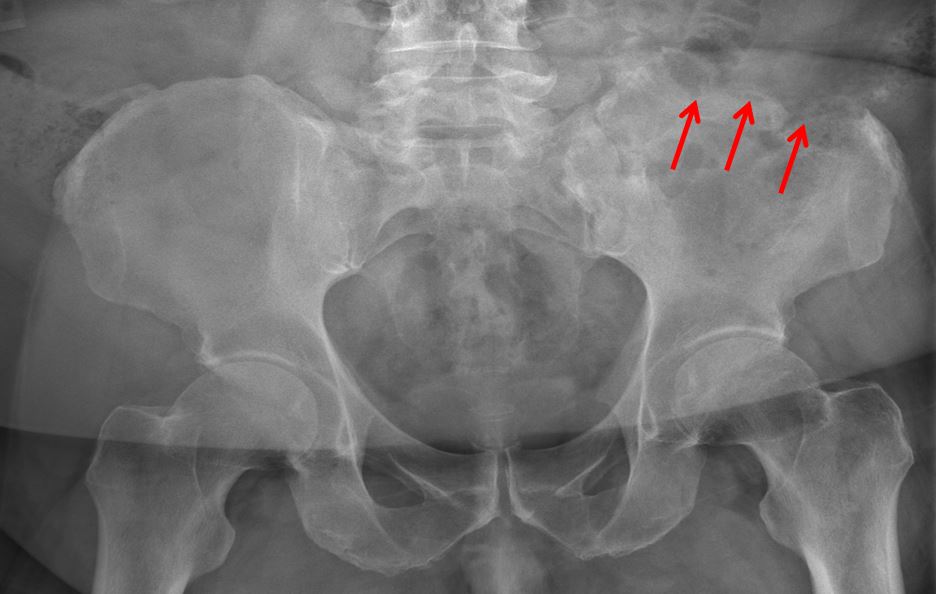

Fig.2: Case 1 - Magnetic resonance imaging demonstrates extensive osteomyelitis throughout left ilium. Stable scattered focal fluid collections seen throughout the left lower quadrant..jpg)